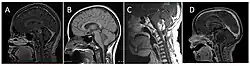

Classification of brainstem gliomas by MRI appearance.

Neuroimaging, such as MRI, is the main diagnostic tool for brain stem gliomas. In very rare cases, surgery and biopsy are performed.